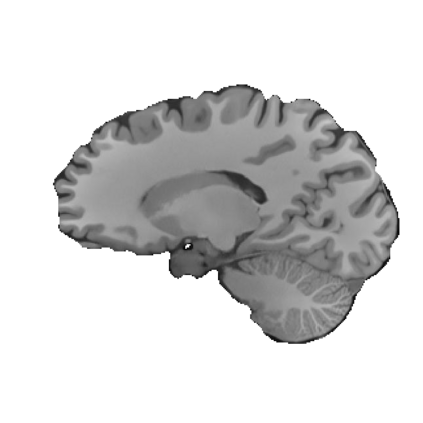

Magnetic resonance (MR) images are often acquired in 2D settings for real clinical applications. The 3D volumes reconstructed by stacking multiple 2D slices have large inter-slice spacing, resulting in lower inter-slice resolution than intra-slice resolution. Super-resolution is a powerful tool to reduce the inter-slice spacing of 3D images to facilitate subsequent visualization and computation tasks. However, most existing works train the super-resolution network at a fixed ratio, which is inconvenient in clinical scenes due to the heterogeneous parameters in MR scanning. In this paper, we propose a single super-resolution network to reduce the inter-slice spacing of MR images at an arbitrarily adjustable ratio. Specifically, we view the input image as a continuous implicit function of coordinates. The intermediate slices of different spacing ratios could be constructed according to the implicit representation up-sampled in the continuous domain. We particularly propose a novel local-aware spatial attention mechanism and long-range residual learning to boost the quality of the output image. The experimental results demonstrate the superiority of our proposed method, even compared to the models trained at a fixed ratio.